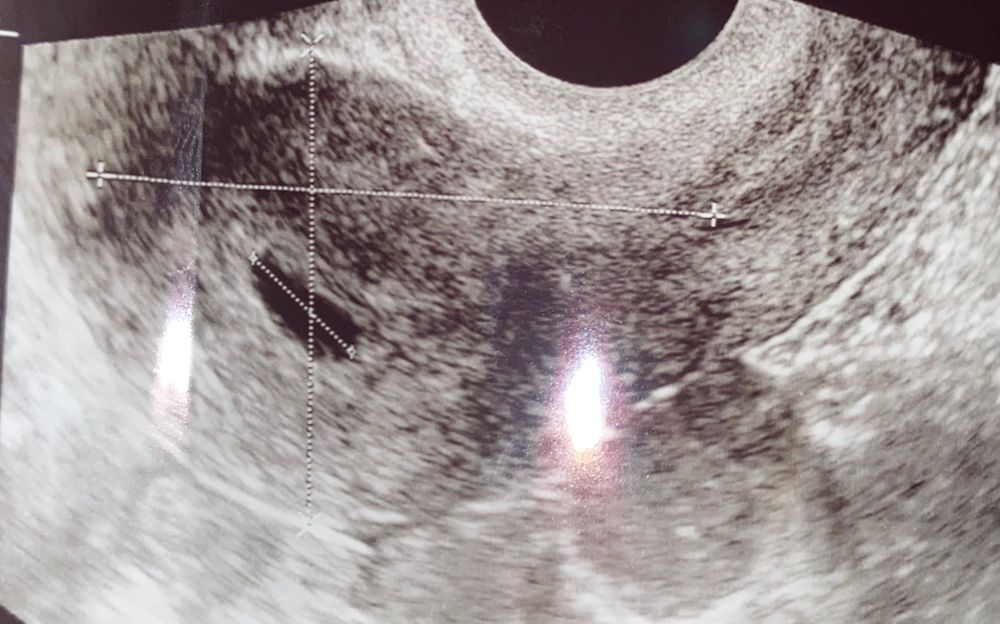

Нет желточного мешочка 19 дпп🥺

Ольга Сергеева, на 24 дпп 17мм, а на 19 когда не нашли жм - 11 мм

Таечка, меня смущает большой размер ПЯ, при таком уже должны увидеть 😞